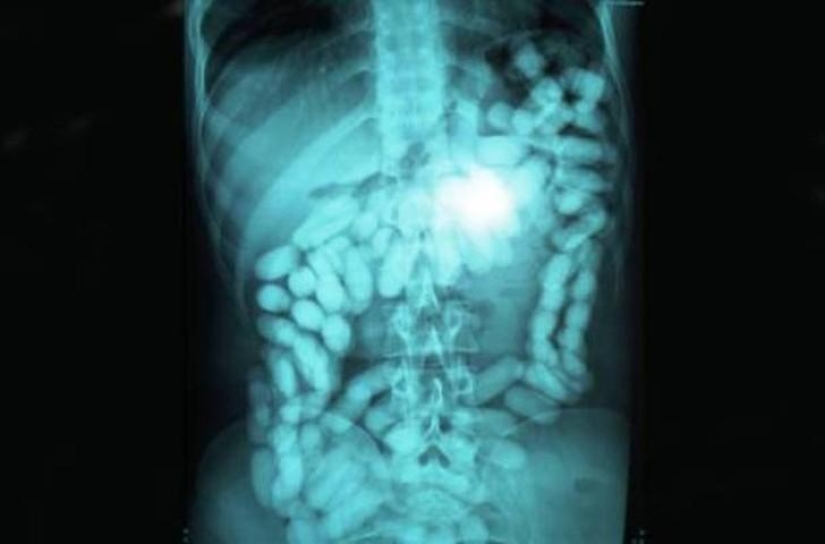

metanfetaminas